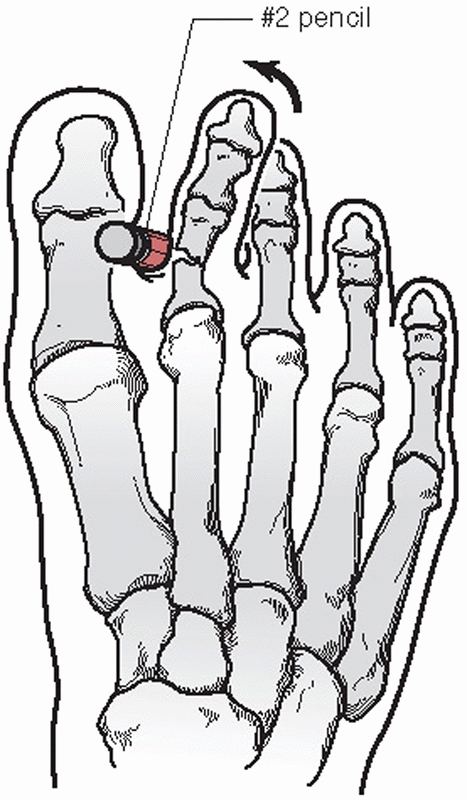

sedation to allow the joint to “unlock.” The patient is placed in the

prone position and the hindfoot is fully plantarflexed. With relaxation

of the peroneal spasm, dorsally directed pressure is placed on the

plantar aspect of the cuboid. At the same time, the forefoot is further

plantarflexed. Another reduction method can be performed with the

patient lying supine and the foot suspended by longitudinal traction

applied to the fourth toe and with the forefoot in slight

plantarflexion. Vigorous activity post reduction should be avoided for

24 to 48 hours.